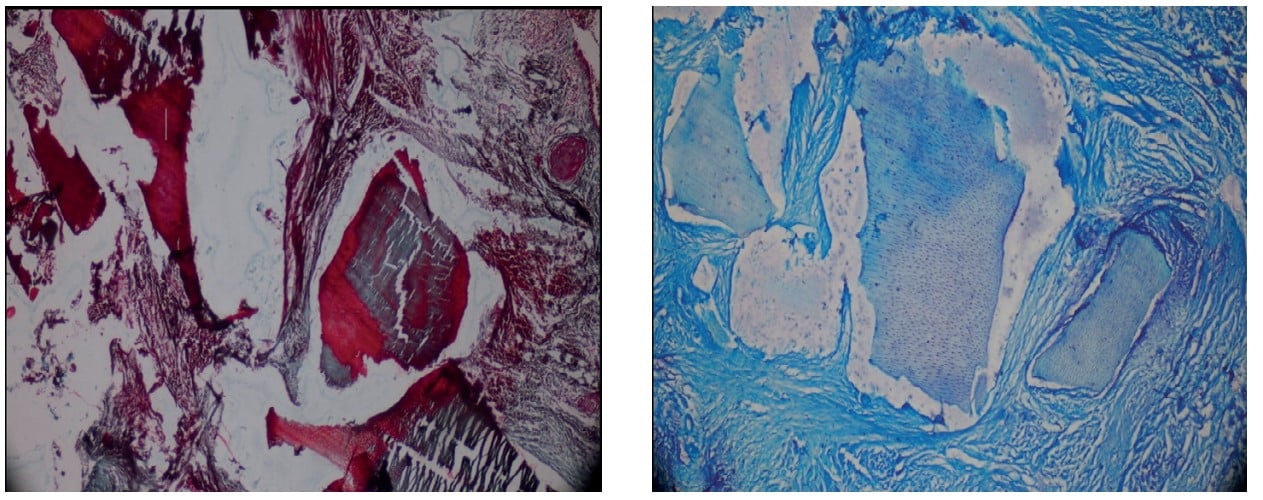

Tooth derived bone graft material. Download Scientific Diagram Tooth-Derived Bone Graft Material Based on the potentials of osteoconduction, osteoinduction, and. Osteogenic capacity of tooth derived (mainly dentin) bone graft material has been shown in many studies with significant. A bone graft is defined as a living tissue capable of promoting bone healing, transplanted into a bony defect, either. With successful extraction of growth factors and bone morphogenic proteins (bmps) from mammalian teeth,. Tooth-Derived Bone Graft Material.